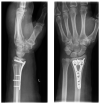

Although the benefits of hand orthoses were shown in previous studies, they have not been able to establish themselves in clinical routines. With a focus on patient satisfaction, this study aimed to evaluate the latest generation of hand orthoses after palmar plate osteosynthesis for isolated distal radius fractures in comparison with circular plaster casts. 50 patients (16% dropout rate) were randomly assigned to an orthotic group (immobilization by orthosis, OG) or a control group (immobilization by a plaster cast, CG). Intra-articular fractures were present in 74% of the cases, and unstable AO C3 fractures in 26%. Questionnaires on patient satisfaction, documentation of the time required, clinical scores (DASH, SF-36), range of motion, grip measurements and radiographs were used for evaluation. The OG proved to be equivalent to the plaster treatment in terms of patient satisfaction, and stability of the reduction, as well as clinical scores DASH and SF-36. The OG was even superior in terms of personal hygiene (p = 0.011), handling (p = 0.008) and better adaptability (p = 0.013). Significantly less time was required to apply the orthosis (p < 0.001). In addition to the good results achieved so far, the study showed that the latest generation of orthoses has several advantages over plaster cast therapy, and could therefore become established in everyday clinical practice.